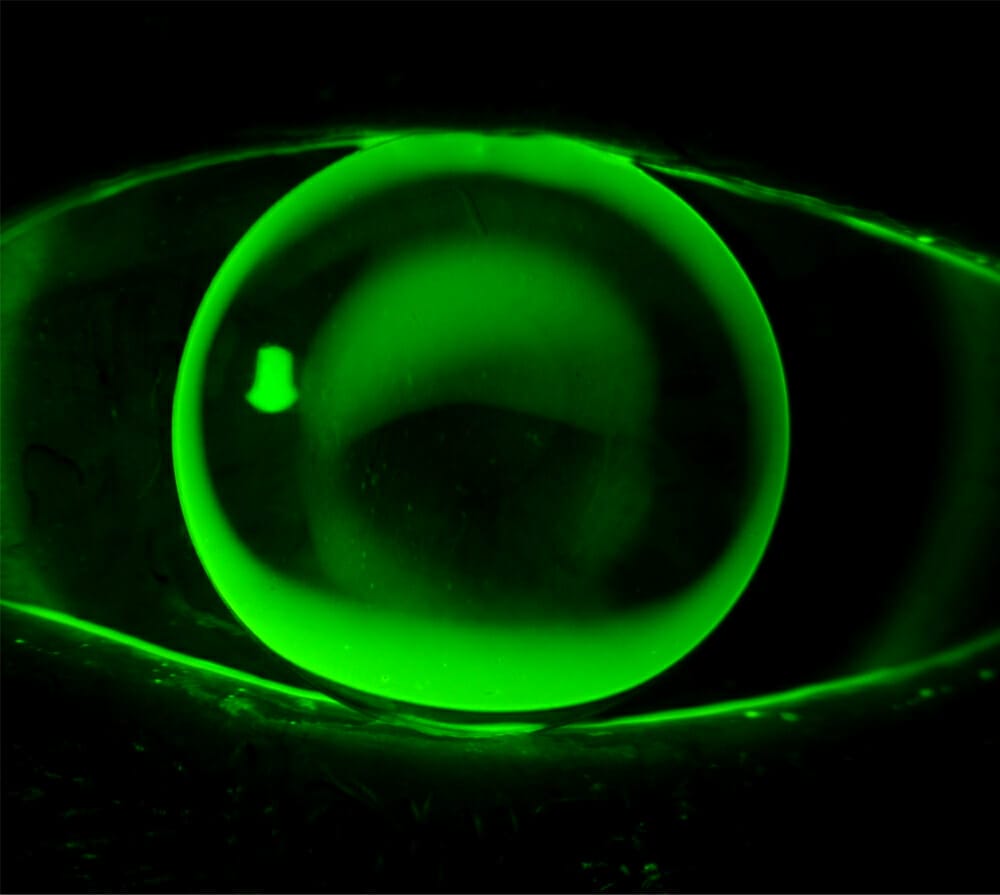

From www.sciencephoto.com

Hard contact lens for keratoconus Stock Image C009/0104 Science Hard Contact Lens For Keratoconus These are hard lenses that create a smooth surface over the irregular cornea, providing clear vision. Rigid gas permeable (rgp) lenses: In this blog post, we will explore the different types of contact lenses for keratoconus. Generally, scleral contact lenses provide the best fit, comfort and visual acuity for someone with keratoconus. These lenses are sometimes called hard lenses, rigid. Hard Contact Lens For Keratoconus.